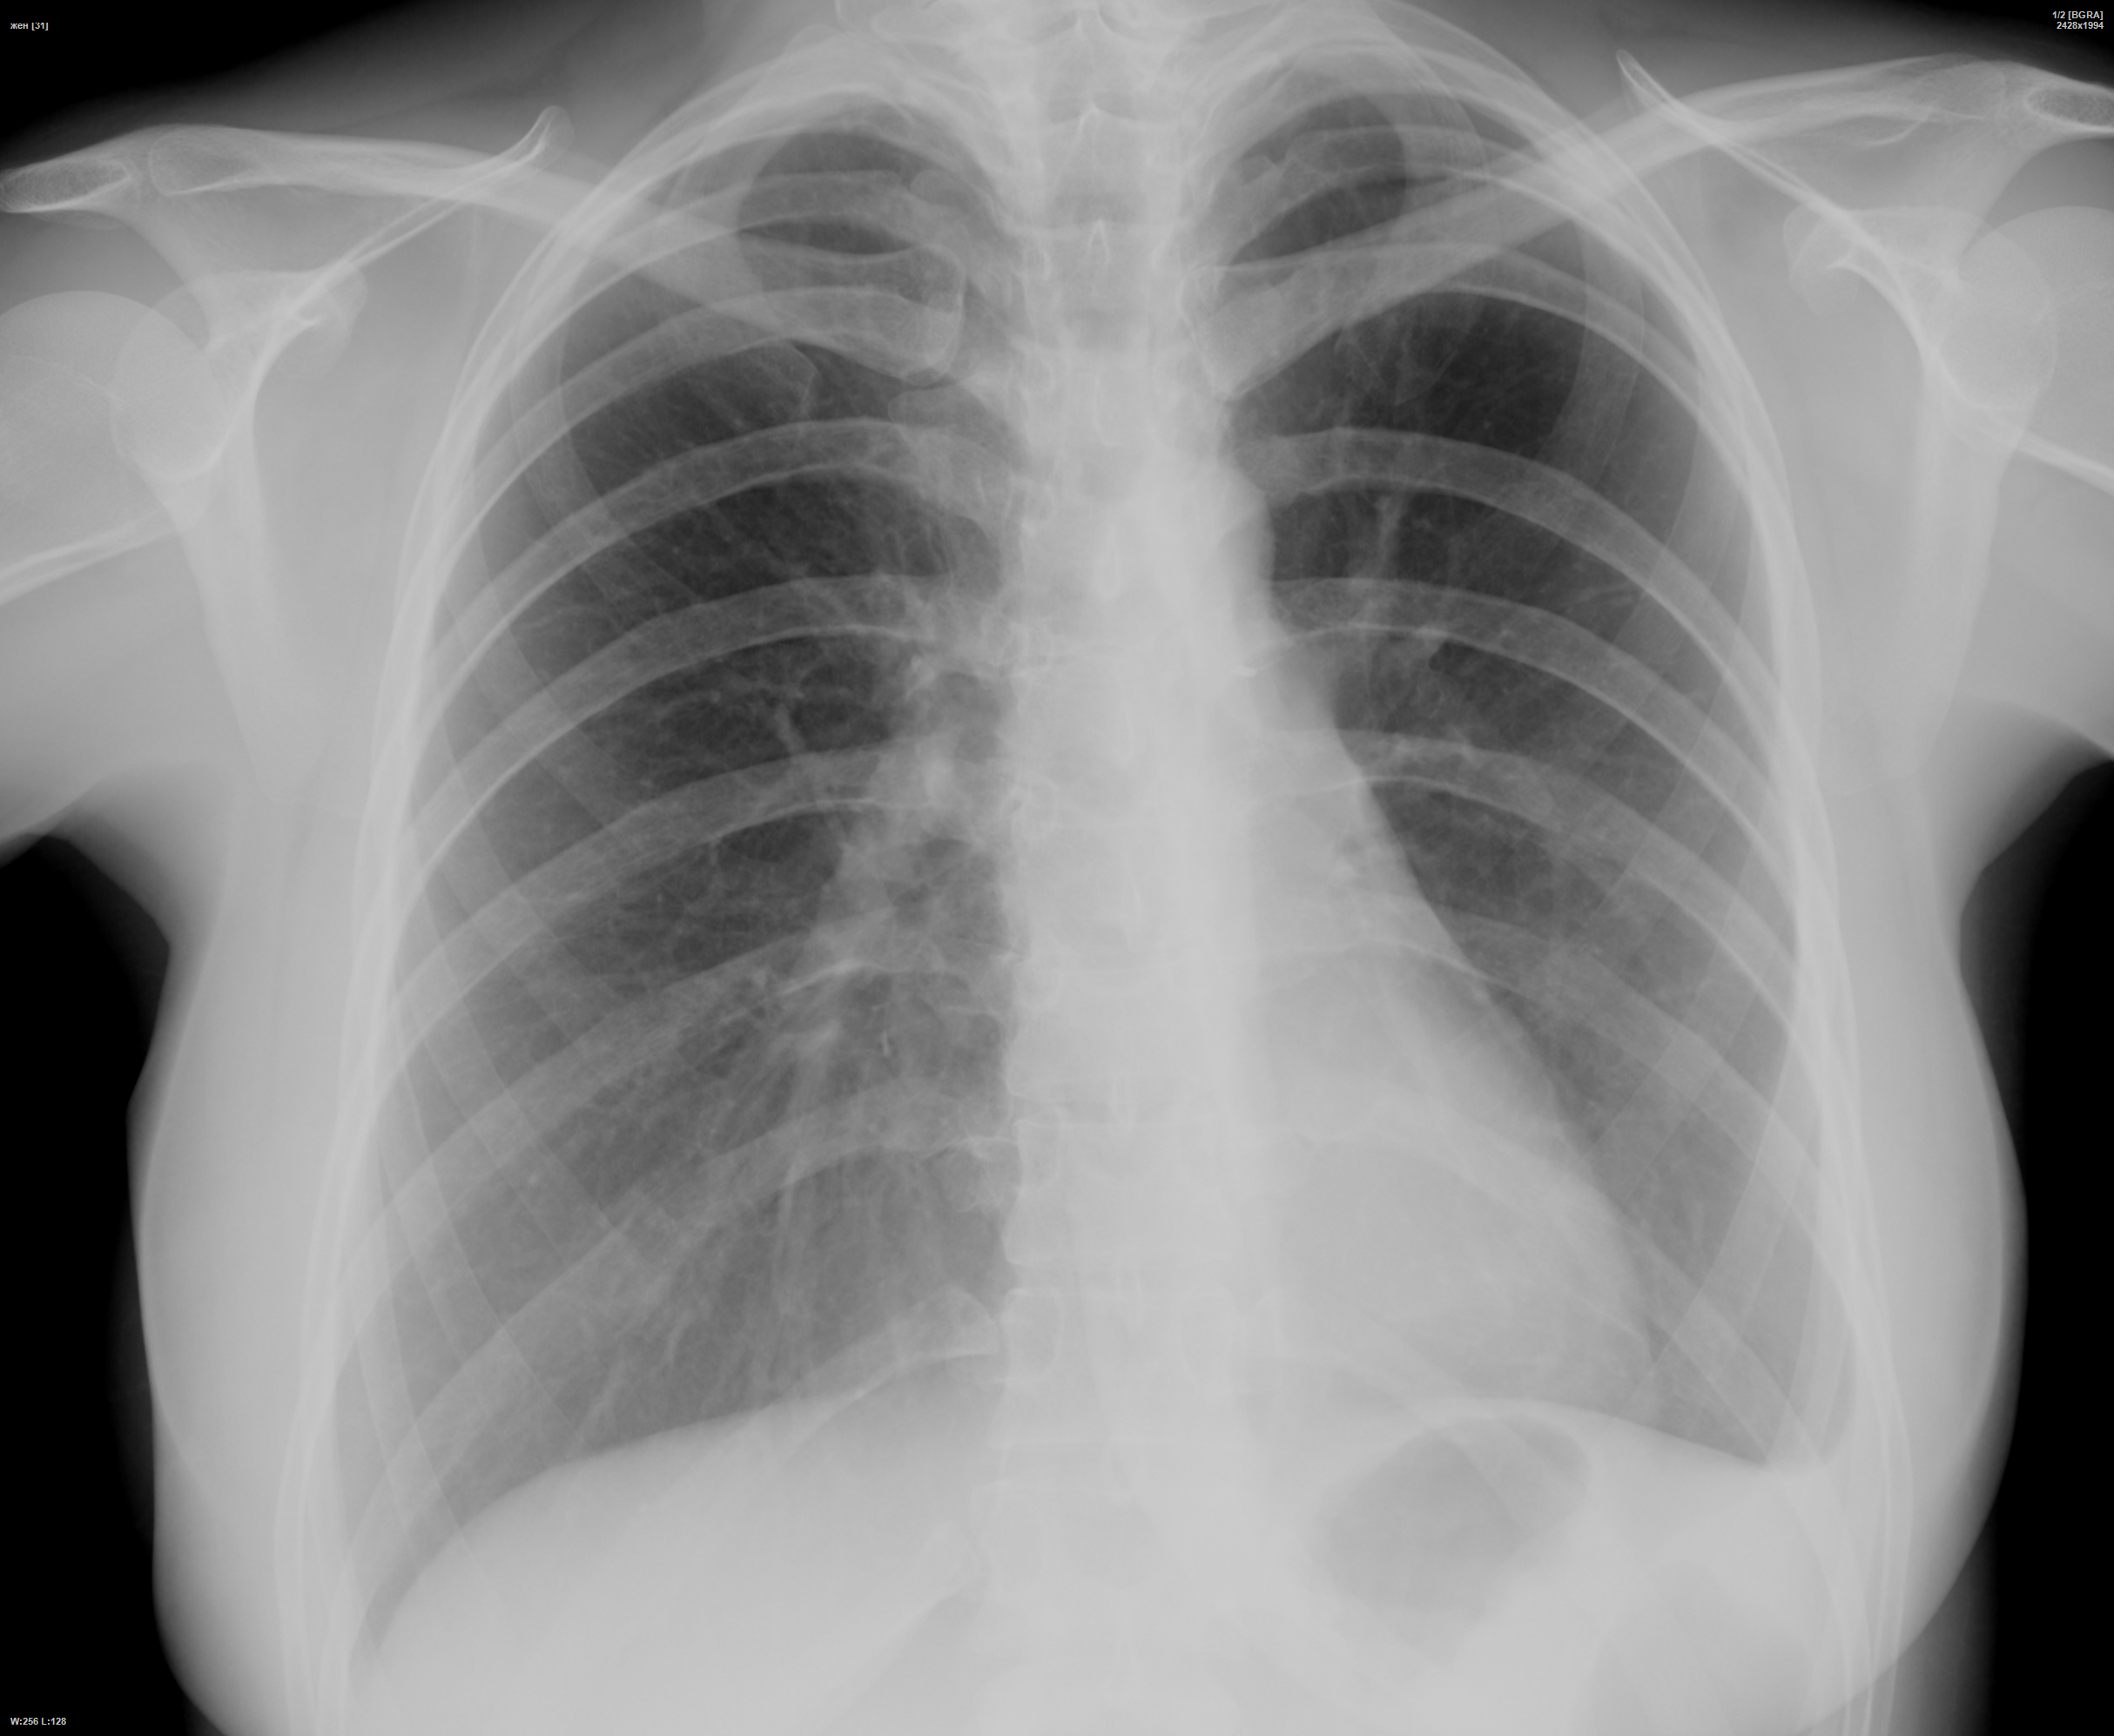

Снимок легких при туберкулезе является важным методом диагностики этого заболевания. На рентгеновских снимках можно увидеть изменения в легких, которые свойственны туберкулезу.

Закрытая форма туберкулеза рентген

Рентген легких

Рентген легких

Рентген легких

Нормальная рентгенограмма ОГК

Фотографии снимков легких при туберкулезе

В данной статье представлены многочисленные фотографии снимков легких при туберкулезе, чтобы помочь вам понять, как выглядят изменения легких на рентгеновских снимках при этом заболевании.